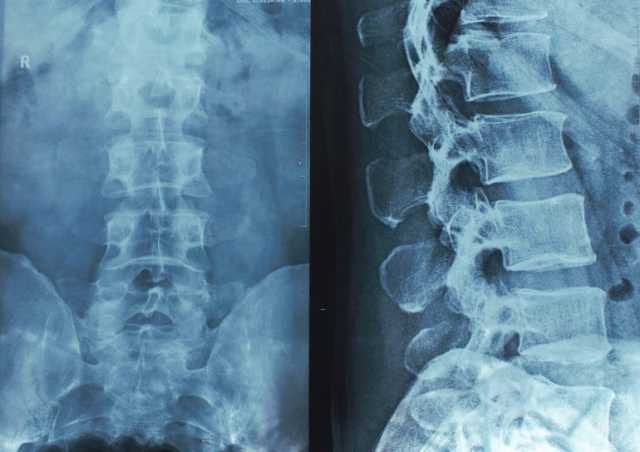

وتقول الدكتورة ويلز في تصريحات للجزيرة نت: " للمرة الأولى، تمكنا من رصد اليورانيوم داخل أنسجة العظام لدى البشر باستخدام جهاز التحليل الفلوري بالأشعة السينية، والقدرة على قياس هذه المستويات في معظم المشاركين يشير إلى وجود تعرض واسع النطاق في المجتمع المحلي".

وتقنية التحليل الفلوري بالأشعة السينية، أداة متقدمة تُستخدم عادة في المواقع الأثرية أو الصناعية، لكنها استخدمت في الدراسة لفحص العظام البشرية ميدانيا دون أخذ عينات أو إتلافها، وتعتمد على قيام الجهاز بإطلاق أشعة سينية عالية الطاقة على سطح العظم، فتتفاعل الذرات داخل العينة وتصدر إشعاعا مميزا يكشف عن العناصر المعدنية المخزنة في النسيج العظمي.

يستخدم هذا التحليل لفحص العظام البشرية ميدانيا دون أخذ عينات أو إتلافها (غيتي)أعلى نسبة بين النساء